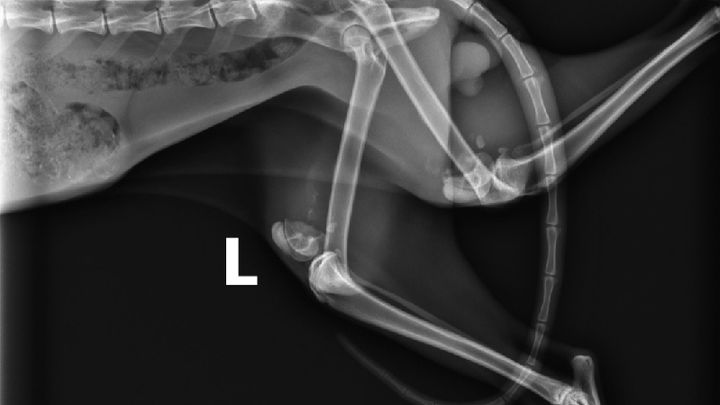

Simon is a one-year-old cat rescued from a neighbor's yard on July 19, 2021. Simon needs life-altering surgery to correct both of his back legs which were broken when he was younger and healed improperly because he didn't receive medial care.

- Two separate surgeries, one for each leg. Total cost 9/29/21 Update: $5400 ($2700 per leg)

- Smooth the top part of the lower bone that sticks out on the inside of his legs. (updated 9/29/21)

- Attach the two parts with a metal plate & screws - As of 9/29/21, we are no longer doing this.

A visit to the vet revealed the problem. Both back legs had been broken at some point and didn’t heal properly because the kitty never received medical help. The vet said it would require a specialist surgeon to correct the problem and it would be expensive. While this was sad to hear, at least kitty was in not in need of critical care like we feared. Even though he was clearly emaciated, he weighed 8 pounds. Blood tests showed him to be FIV+. He got his vaccines and rabies shot.

On August 16, Simon had his consultation with the surgeon. After discussion of options and risks, we scheduled the first surgery for 8/24. Estimated cost per leg is $4000. Cost updated to $2700 per leg as of 9/29/21.